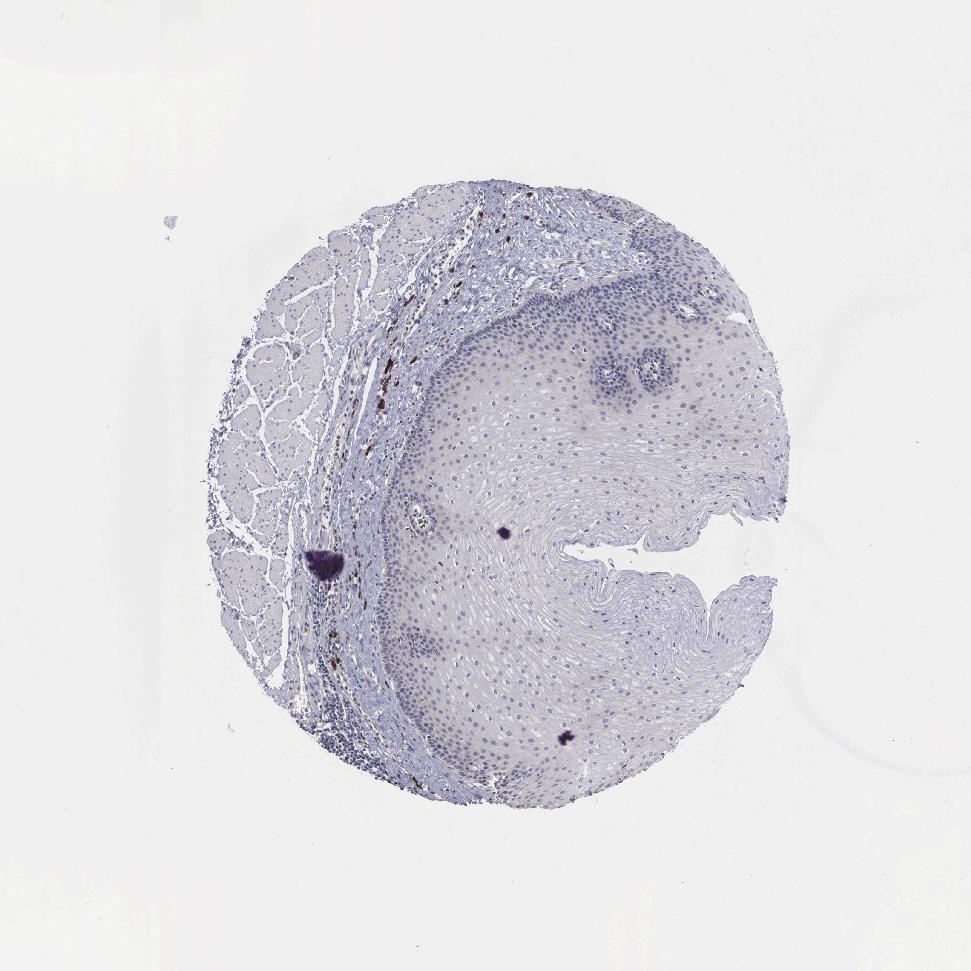

ESOPHAGUS - Antibody stainingi

Antibody staining in the annotated cell types in the current human tissue is reported as not detected, low, medium, or high, based on conventional immunohistochemistry profiling in selected tissues. This score is based on the combination of the staining intensity and fraction of stained cells.

Each image is clickable and will lead to virtual microscopy that enables deeper exploration of all samples and also displays staining intensity scores, fraction scores and subcellular localization as well as patient and tissue information for each sample.

Antibody HPA000603Antibody CAB025604

Squamous epithelial cells Not detectedLow